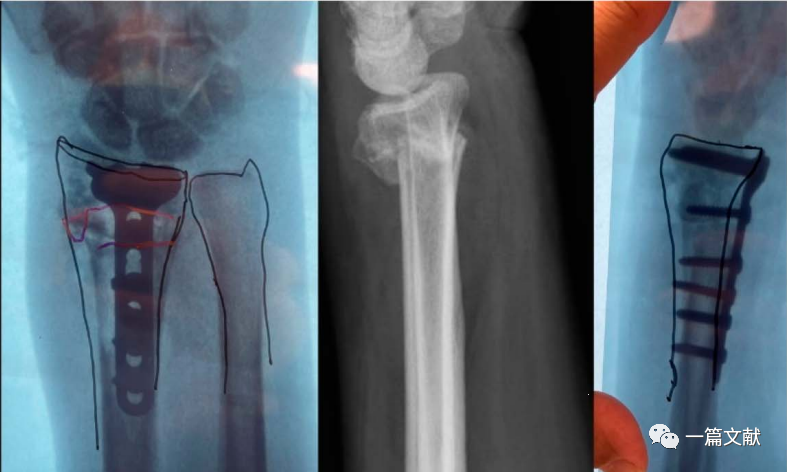

骨折畸形愈合的截骨矫形手术

此法可极大的简化截骨矫形手术过程,如下图:

最后为该患者矫形术后的下肢全长位片,患肢力线恢复满意